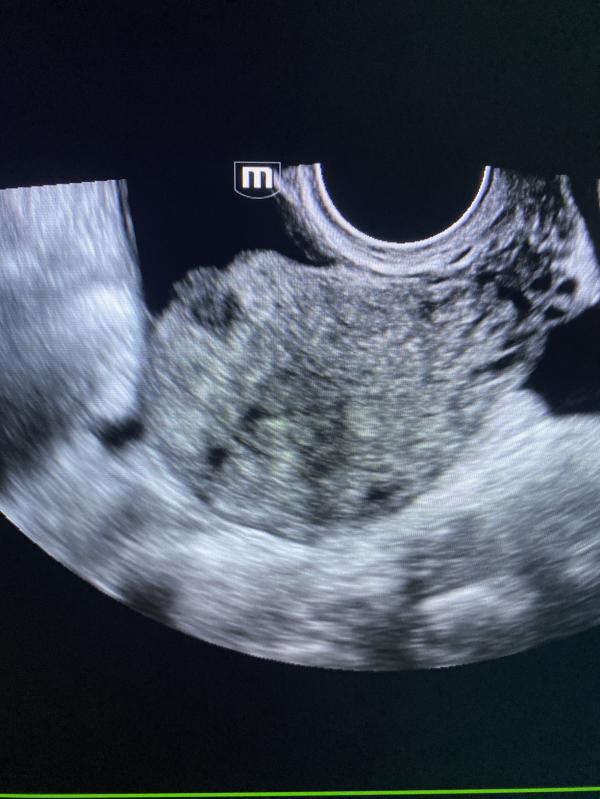

Узи миома матки: можно ли увидеть миому на снимке УЗИ? Случаи миомы и камней в почках

Можете на узи снимке увидеть миому матки?

Сегодня было много миом .

Вчера день был богат на камни в почках.